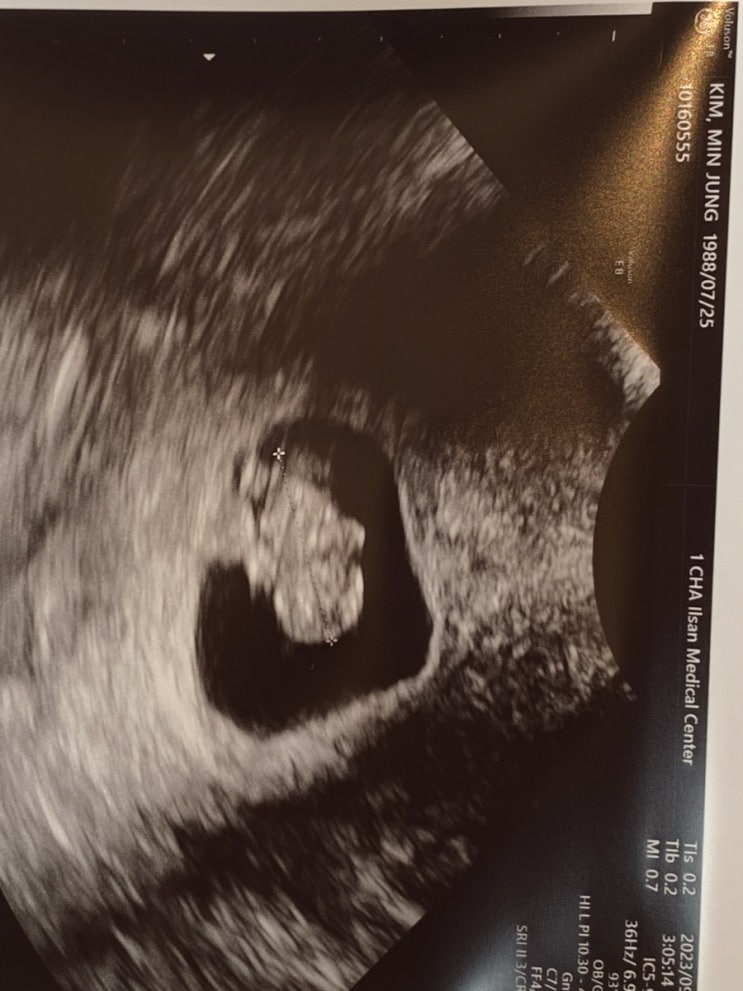

양가 부모님께 서프라이즈 임밍아웃하기~!♡

병원에서 임신 확인서도 받았고~ 이제 양가 부모님께 어떻게 임밍아웃 할지 고민고민!! 남펴니와 둘 다 두...

청용띠 아기 6-8주차 이야기(8월, 9월) 임밍아웃썰

이미 출산하고 아가가 태어난지 한 달이 넘어 신생아를 졸업했지만 뒤늦게 올려보는 임신 이야기☺️ 임신 ...

[임신 5주차] 아직은 실감이 안나 + 임밍아웃 대실패

친구의 첫 임신 선물 임신을 했다는 사실을 남편에게만 알리고 아무에게도 말해주지 않고 있었는데 중학교...

임신 극초기 4주차 5주차 / 부모님 임밍아웃

안녕하세요 ? 저희에게 결혼 2년 차에 아기천사가 찾아왔어요 ..?? 그래서 임신 초기 증상을 기록...

[임신 9~10주차]부모님 임밍아웃+선홍색 혈 비침으로 병원 급방문

임신 9주차 어버이날 기념으로 임밍아웃 결정! 아주 타이밍도 좋쿠로 이것저것 짜잘한 소품들을 준비할까 ...